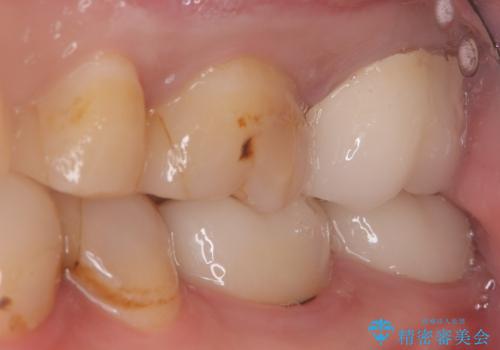

【セラミッククラウン】インレーの下の大きな虫歯

- レントゲンにて昔入れたインレーの下に虫歯が見つかった患者様です。

歯髄に近接する虫歯でしたが、根管治療は必要なくクラウンにて修復を行うことができました。

歯髄に近接する虫歯の場合、痛みなどの症状が出ることがあります。